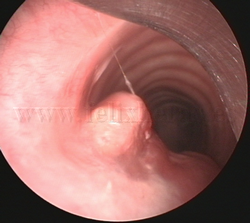

Fotorresección

con láser |